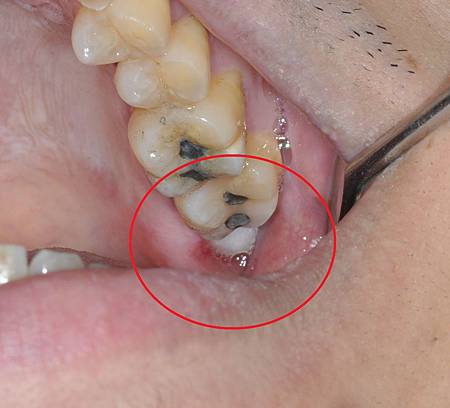

拔完牙在原本牙齒的位置會是一個洞

如果有縫合則會有線頭

若在拔牙同時使用膠原蛋白治療

拔牙傷口就會是滿的不會是空洞

因為血塊會很穩固的充滿拔牙窩

沒有一般拔牙後的深洞

不會有食物殘渣跑入傷口